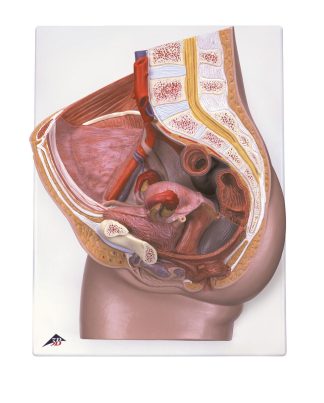

Bäcken manlig – modell

Art.nr: 123646

Snitt av manligt bäcken. Levereras på en bottenplatta som ger möjlighet att monte...

2 150,00 kr2 687,50 kr

Snitt av manligt bäcken. Levereras på en bottenplatta som ger möjlighet att monteras på väggen för enkel visning i klassrummet.

Se manual för mer information.

Artikelnummer: 123646